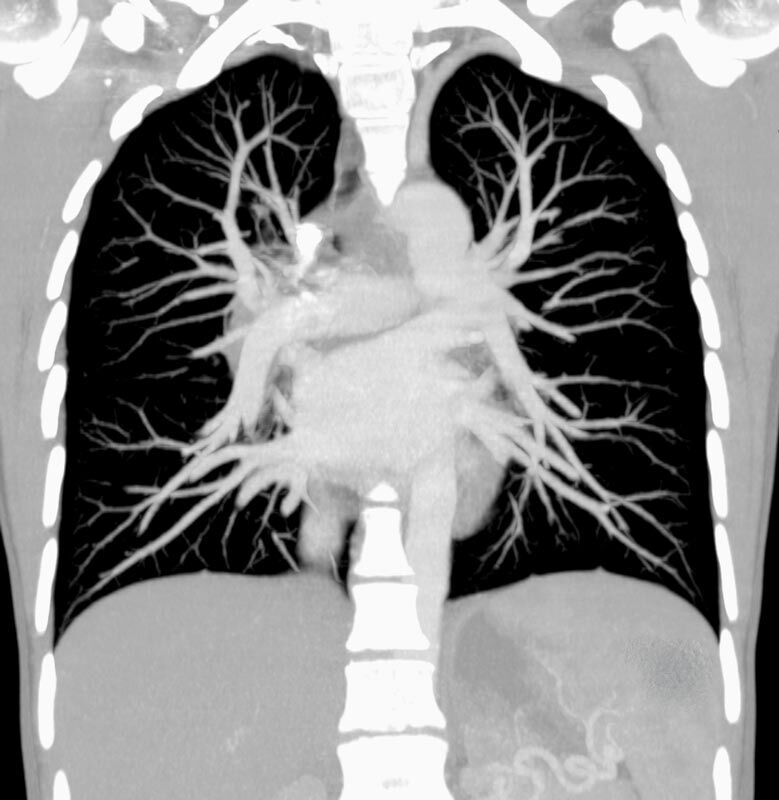

Thorax (Brustkorb)

• Entzündungen oder Tumore des Mediastinums und der Lunge

• Lungenembolie- Diagnostik

• hochauflösende Darstellung des Lungenparenchyms zur Abklärung chronischer interstitieller Erkrankungen wie z. B. Fibrosen, Emphysem, Bronchiektasen